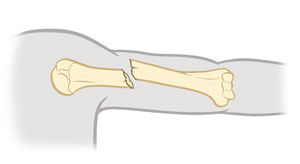

Displaced fracture

Bone fragments are not lined up. A gap exists between both ends of the broken bone.